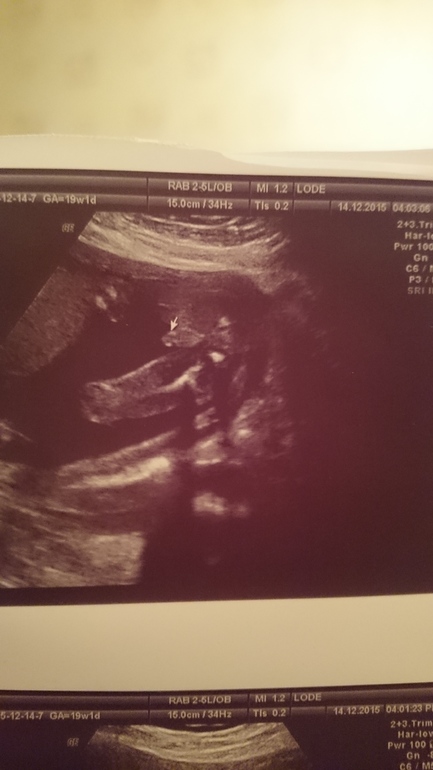

Кто же у нас?😏

Это первый скрининг, врач сказала 50 на 50 (узи делала бесплатно в жк, и поэтому думаю что врач сильно не напрягалась)))

Девочки,знающие, может вам что то будет понятно?😁😁

Срок на время узи был 12.6 (по мес. 12.2)

Половой бугорок не различим, по углу его наклона определяют пол на этом сроке. А у вас при таком ракурсе не видно

Алёна, да дело то даже не в качестве, просто фото на котором видно пол, должно быть сделано со стороны попы, у меня так было. А в таком ракурсе никто и никогда не увидит)

А у вас, я так понимаю стандартное фото, когда бочком всего малыша видно

Первый скрининг в 10-12 недель совсем не показательный в плане пола. Тут дело не во враче. На этом сроке половые органы девочки и мальчика внешне очень похожи. Бугорок может быть либо будущим пенисом, либо клитором. К 17 неделям уже будет возможно определить пол без проблем.